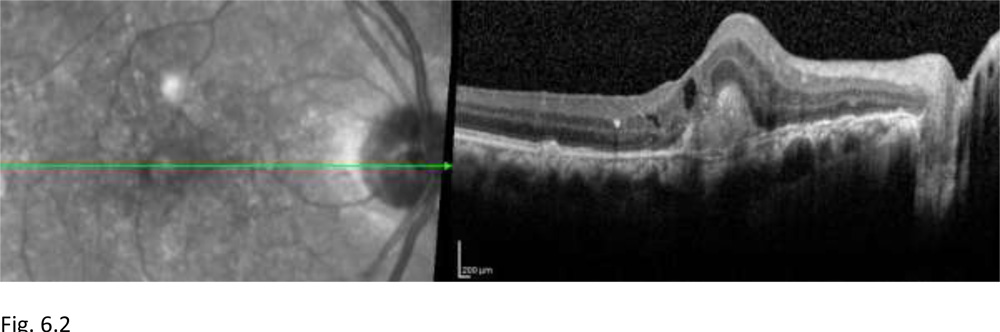

Figure 6.2: Post 3-monthly loading dose Anti-VEGF therapy at 24 months. The patient did not develop any recurrences following the loading dose therapy, thus not requiring any further Anti-VEGF therapy. OCT of OD shows reduction in the subretinalneovascular membrane, disappearance of the subretinal and intraretinal fluid pockets, residual subretinal scar at fovea can be seen.